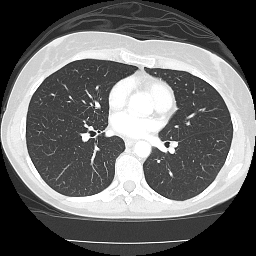

MUÑOZ BARRIENTOS, ANTONIO

1006289633

AUN100628

sábado, 22 de marzo de 2025

COLUMNA DORSAL Y LUMBAR AP Y LATERAL

11/Mar./2001

A QUIEN CORRESPONDA

AGS UNIVERSIDAD

9466, 9468